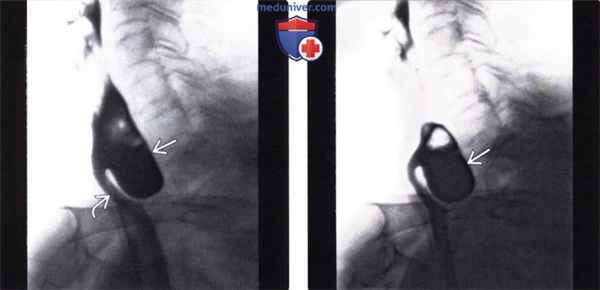

(Слева) На рентгенограмме, полученной во время рентгеноскопии, определяется типичный дивертикул Ценкера в виде «слепого» выпячивания стенки в области перехода глотки в пищевод (приблизительно на уровне 5-6 шейных позвонков). Пищевод смещен в сторону, его просвет сдавлен заполненным дивертикулом.

(Справа) На рентгенограмме, полученной чуть позже, определяется, что дивертикул остается заполненным контрастом и после прохождения бариевой взвеси, просвет пищевода до сих пор сдавлен извне заполненным дивертикулом.